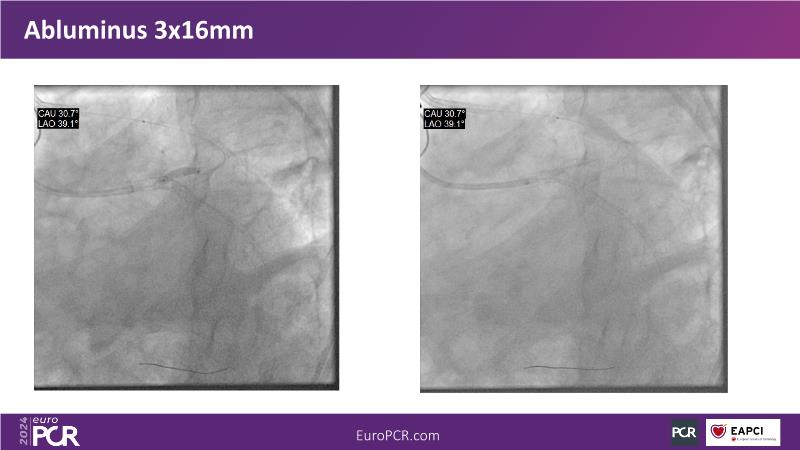

Watch this session to gain case-based insights on using DCBs in complex settings. Learn valuable tips and tricks for optimal DCB application, including the best timing and situations for their use. Discover how to effectively implement a hybrid strategy that combines DES and DCB when needed.

- To get a case based experience on how to use a DCB in complex settings

- To learn about tips and tricks on how and when to use a DCB: the ideal time and situation of DCB application in various complexities

- To utilise the hybrid strategy approach Combining DES and DCB when the situation demands